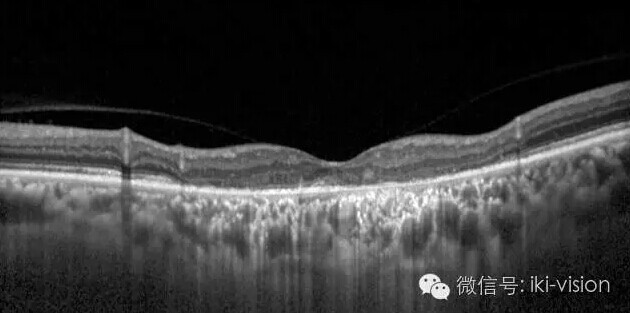

3.OCT检查:右眼(上图)黄斑

中部IS-OS层光反射带消失,外

界膜破坏,RPE萎缩。左眼(下

图)大致同右眼

该患者诊断:双眼萎缩性AMD。

疑问:该患者右眼0.2,左眼0.3

的视力,黄斑中部弥漫性地图萎

缩(GA),OCT显示黄斑中部视

细胞层及RPE层萎缩,难以解释

患者右眼0.2左眼0.3视力。 于是